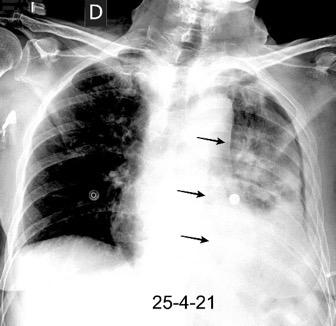

Tromboembolismo pulmonar.

Frecuencia del derrame:

Rx: 32%. TC: 47%

Unilateral. 85%

< 1/3 del hemitórax: 90%

Todos exudados

58% con eritrocitos

21% tabicación lo que causa demora en el diagnóstico

TEP. Empiema pleural. Atelectasia redonda

Porcel JM et al. Analysis of pleural effusions in acute pulmonary embolism: radiological and pleural fluid data from 230 patients. Respirology 2007/ Iguchi T et al. Desquamation of the subpleural lung parenchyma caused by empyema after pulmonary embolism: A case report. Respirol Case Rep. 2022 .